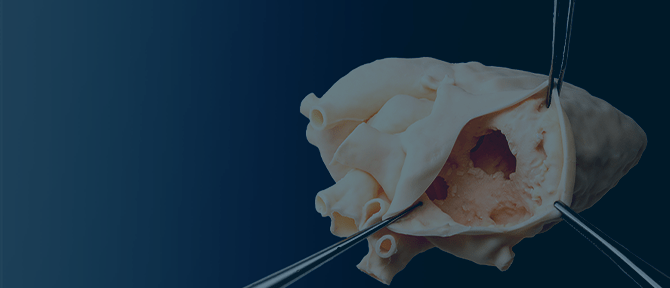

リアルな生体感

人体と同等の含水率のため、実臓器の触感や柔軟性など、リアルな生体感を得ることができる。